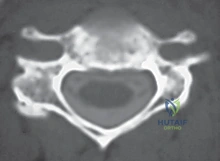

- التصوير بالرنين المغناطيسي (MRI): وهو الفحص الأهم لتحديد موقع الانزلاق الغضروفي بدقة ومدى انضغاط الأعصاب.

- التصوير المقطعي (CT Scan): قد يُطلب للحصول على تفاصيل أدق للتشريح العظمي.

باستخدام أدوات ميكروسكوبية دقيقة، يتم تفريغ وإزالة القرص الغضروفي التالف بالكامل. يتم كشط الغضروف حتى الوصول إلى السطح العظمي للفقرتين العلوية والسفلية.